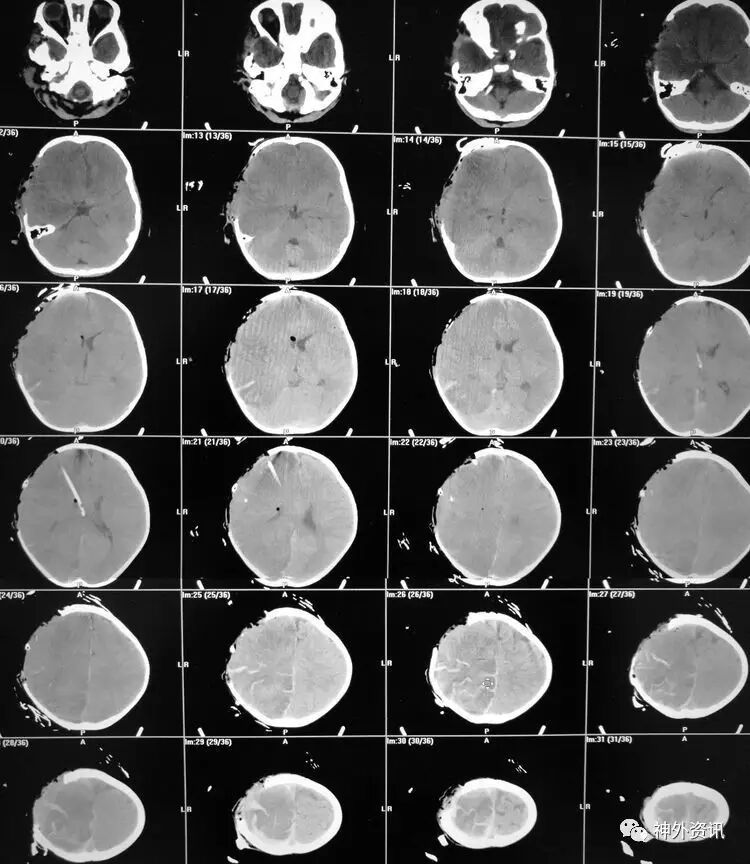

胸部CT及超声显示双肺底存在肺不张:

前胸超声:

肺底超声: